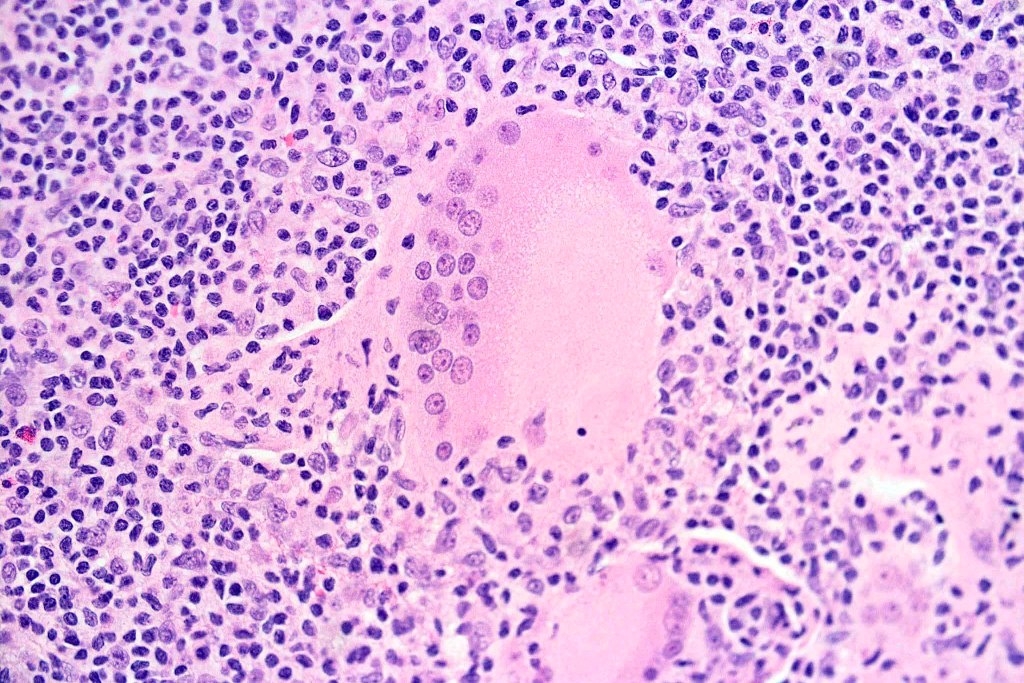

•Atypical, hyperchromatic lymphocytes, Sezary cells, histiocytes, plasma cells, eosinophils & characteristic multinucleate giant cells (innumerable nuclei resembling a shoal of fish)

•Lymphophagocytosis is generally marked

•Discrete granulomata often evident & in some cases may be the dominant feature obscuring the background lymphomatous infiltrate